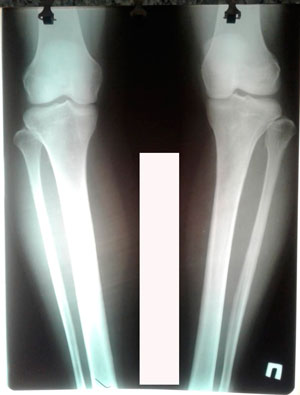

перед крутками

image-26-08-20-06-24-1.jpg